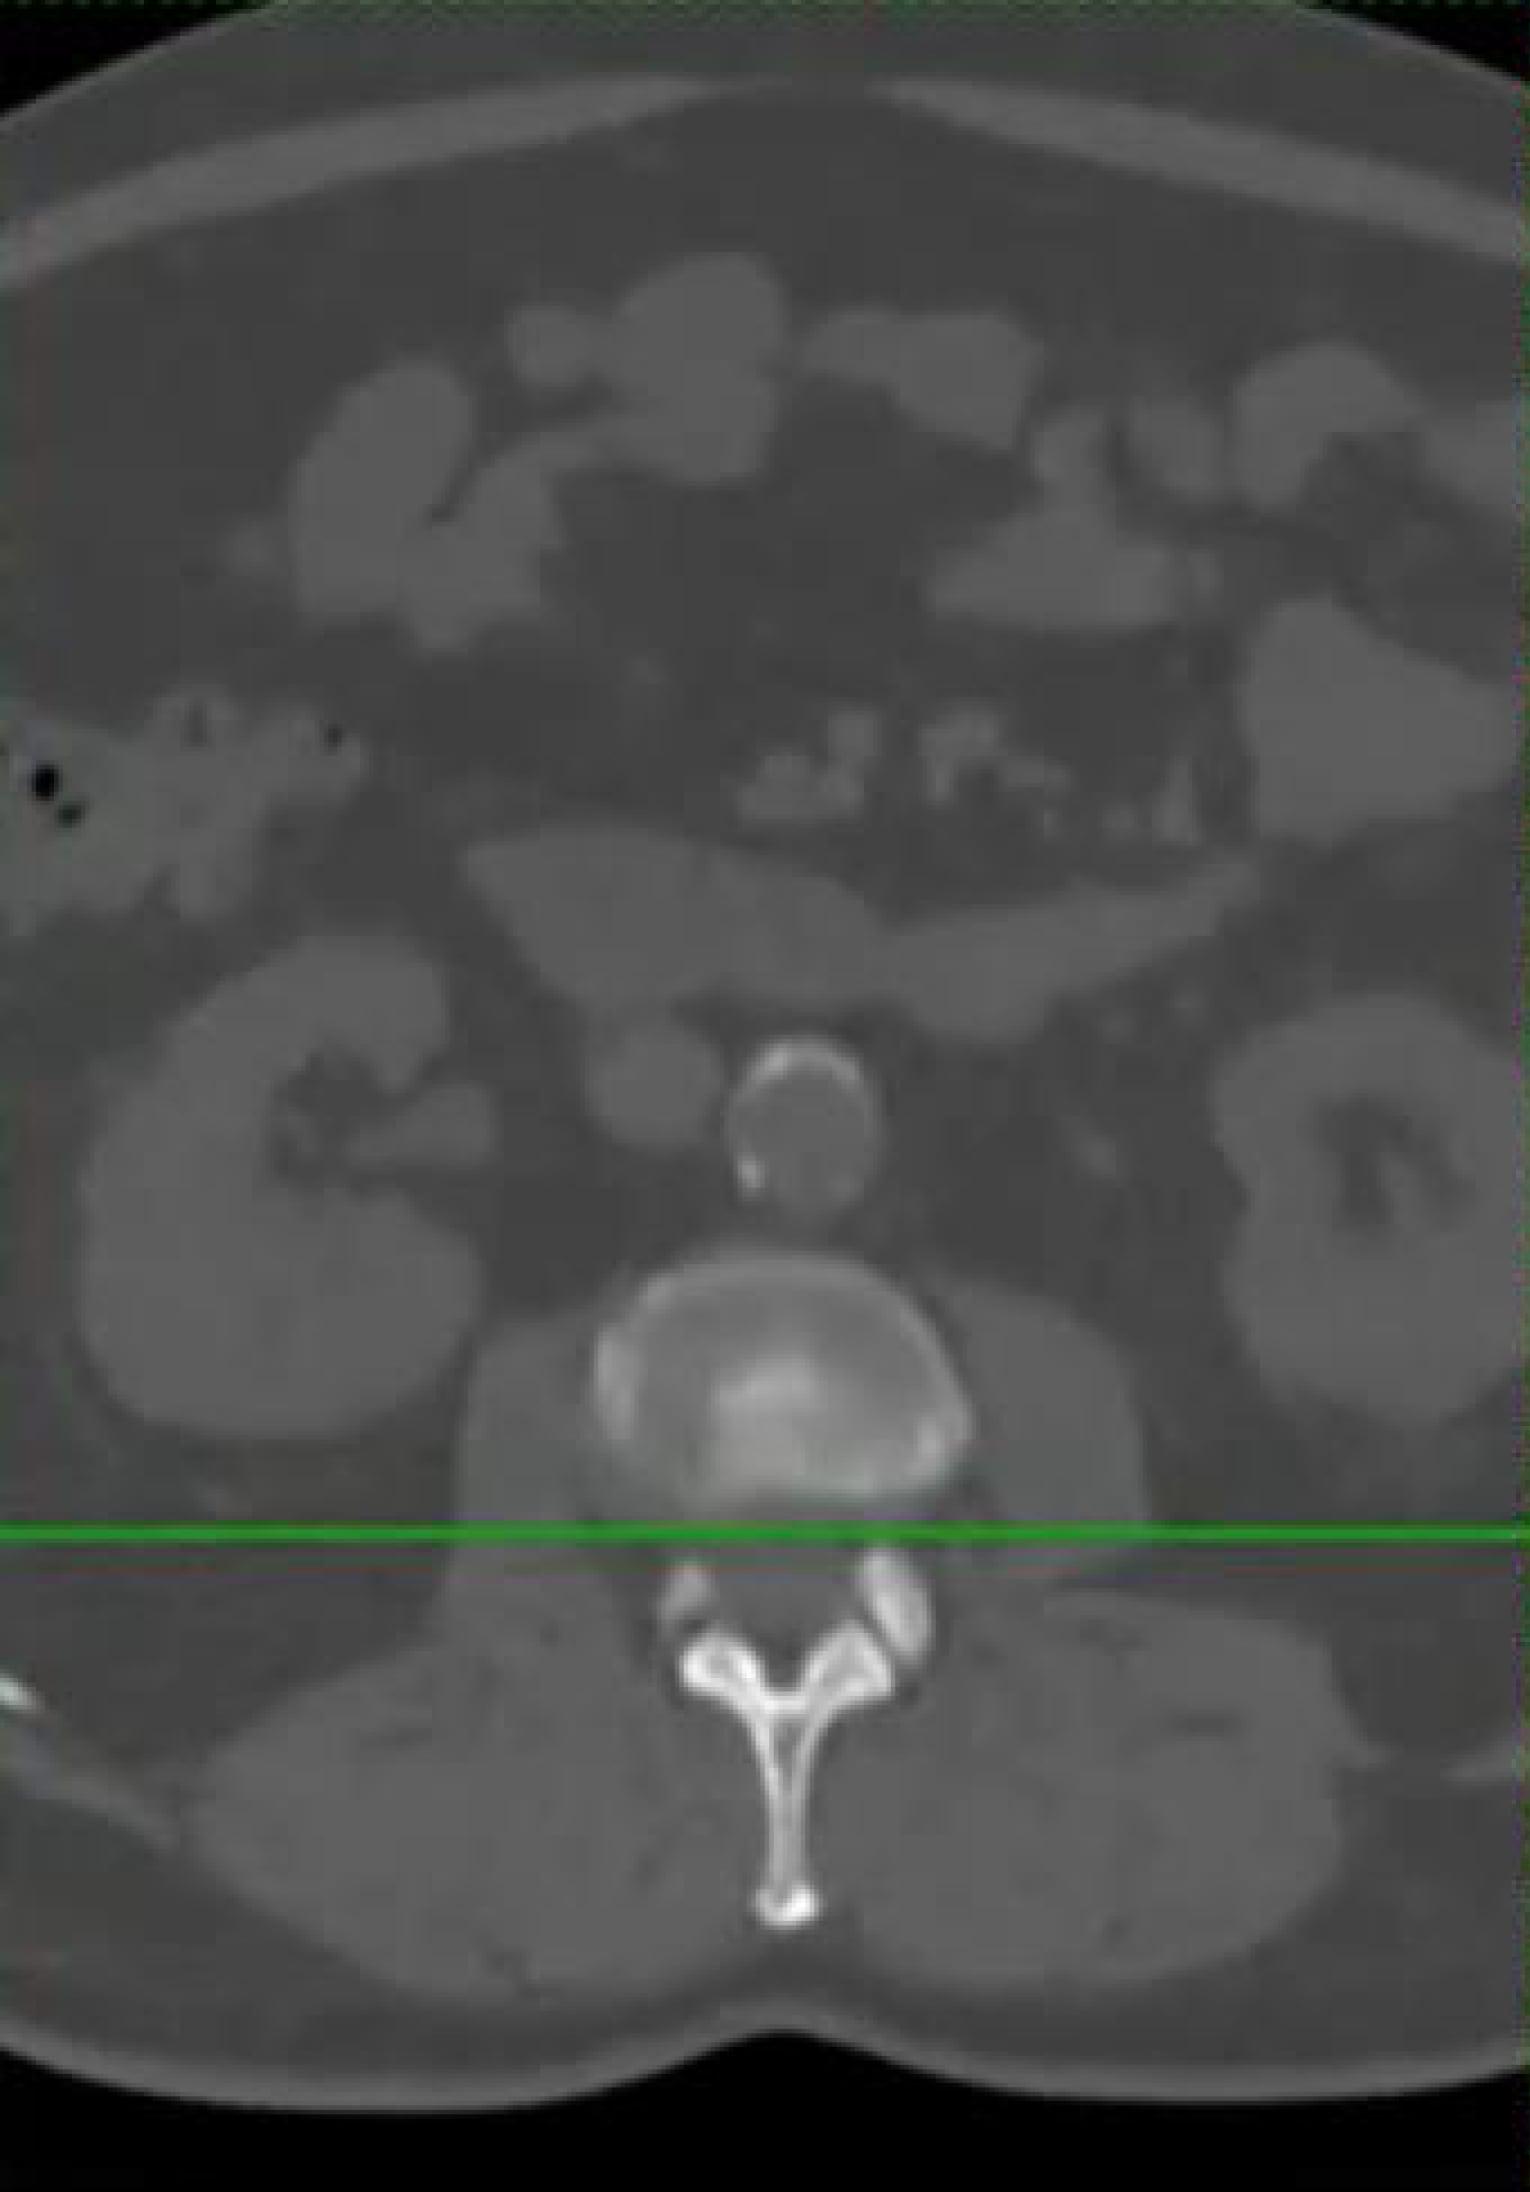

Neueste Technologie in der intraoperativen Bildgebung

Diese Methode ist insbesondere bei komplexen Operationen von großem Vorteil, da sie eine genauere Überwachung des chirurgischen Eingriffs ermöglicht. Zudem können im Verlauf der Operation wichtige Informationen und Daten erhoben werden, die für die weitere Behandlung von großer Bedeutung sind.